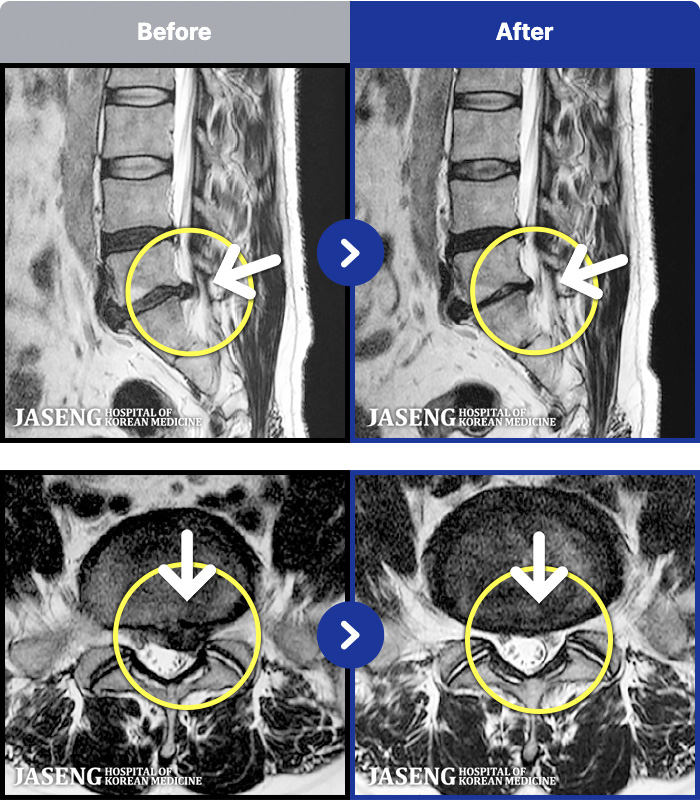

- MRI ġ

MRI ġ

191 MRI ũ ʸ Ȯϼ.

㸮 , , ⸳ Ƹ

[Կñ:25.08.06~26.02.24]

[_㸮ũ] ٸ 㸮 ȹٷ , Բ 㸮 ־ ߴ.

No.190

ȸ 39

2026.03.20